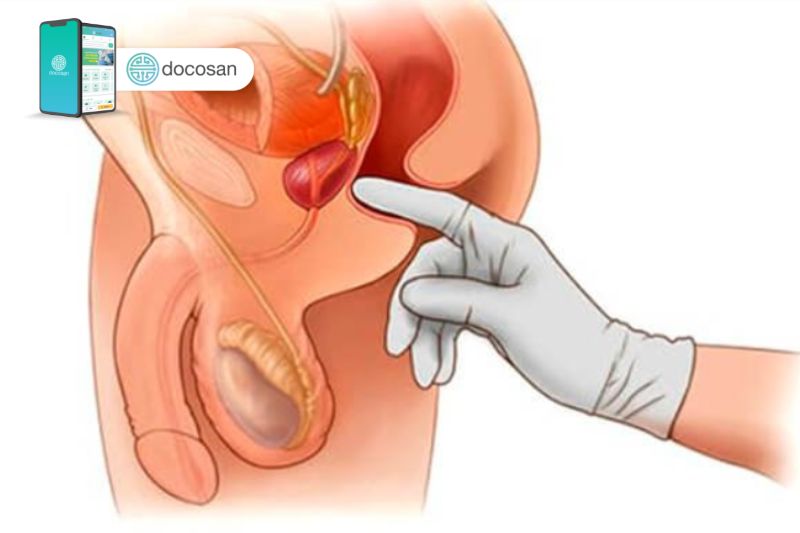

Các phép đo kích thước phì đại tiền liệt tuyến cần có độ chính xác cao để xác định được giai đoạn tiến triển của bệnh và quyết định phương pháp, cho nên người mắc bệnh nên đến các cơ sở y tế uy tín gặp bác sĩ nam khoa có tay nghề để thăm khám và được làm xét nghiệm trước khi điều trị.

Đánh giá kích thước phì đại tiền liệt tuyến theo từng giai đoạn là bước rất quan trọng để xác định chẩn đoán mức độ của bệnh để từ đó chọn lựa biện pháp điều trị tối ưu. Vậy nên nếu bạn đang gặp phải các dấu hiệu của bệnh thì hãy đi khám bác sĩ nam khoa càng sớm càng tốt. Bạn sẽ được thăm khám kỹ lưỡng và thực hiện các xét nghiệm cần thiết để xác định rõ được kích thước phì đại tiền liệt tuyến.